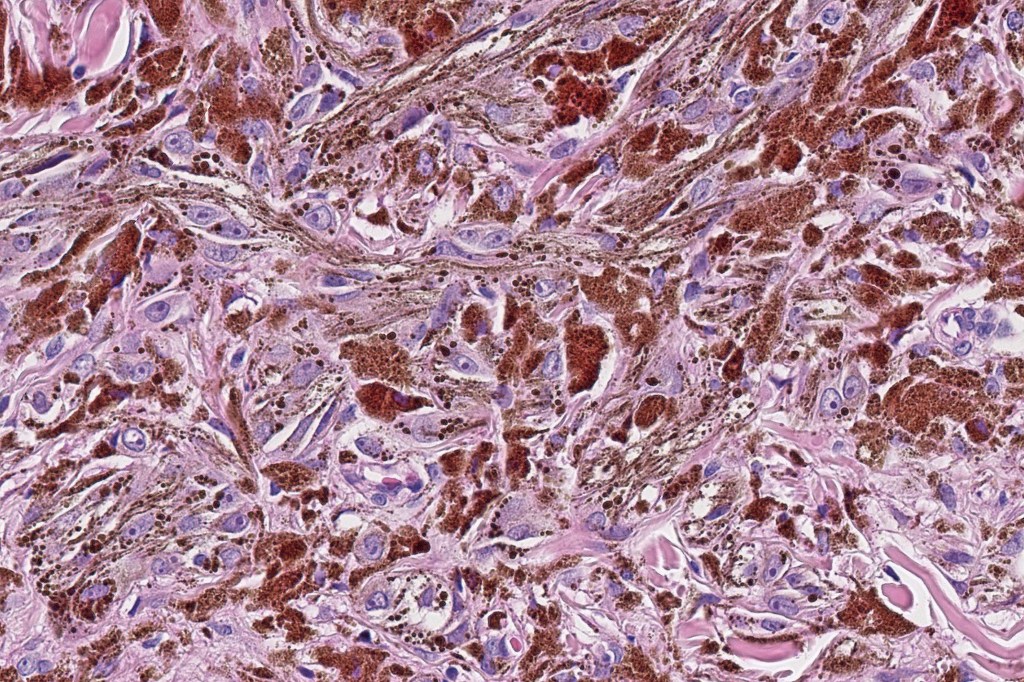

Combined common melanocytic nevus and pigmented epithelioid melanocytoma